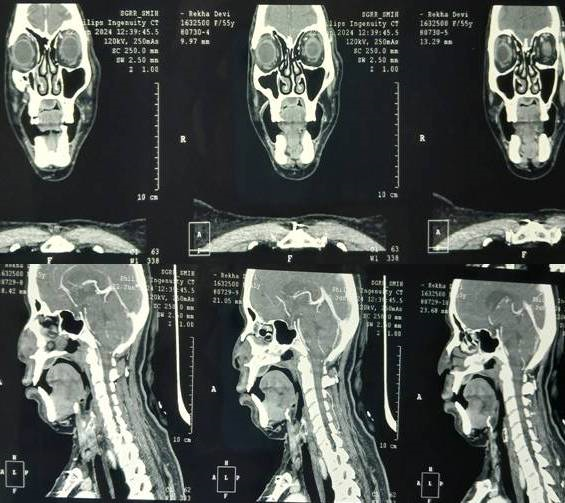

Figure 3a Sections show tissue exhibiting periapical granuloma with adjacent normal salivary gland tissue (H and E, X10).

Figure 3b Sections show the proliferation of capillaries admixed with fibroblasts and lympho mononuclear infiltrates (H and E, X10).